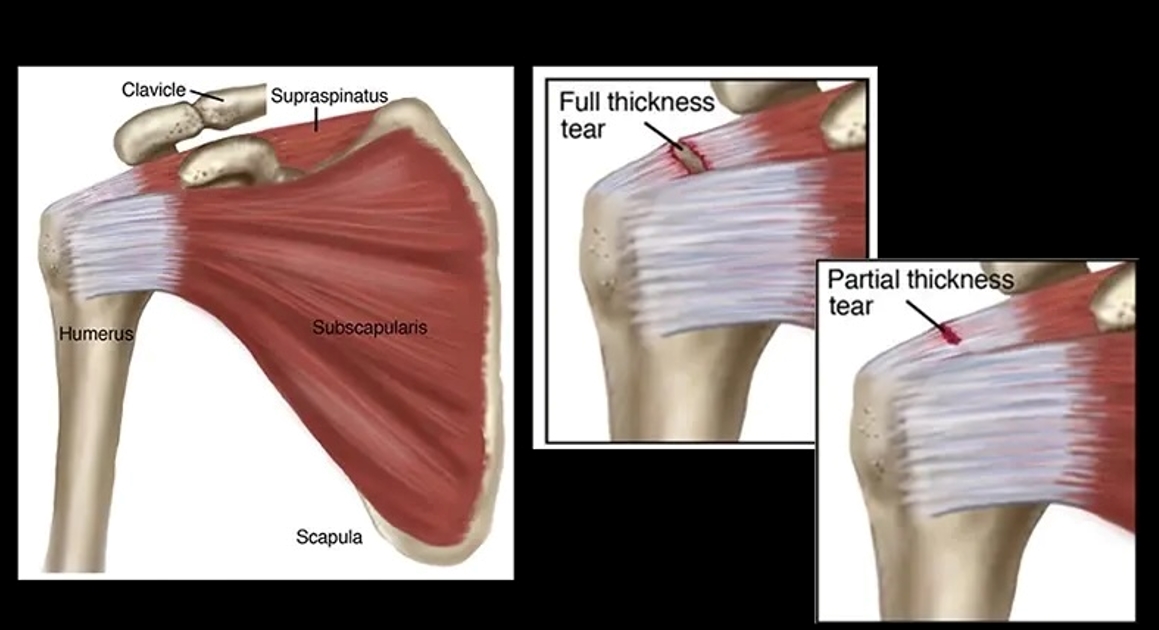

肩袖肌群撕裂的類型

肩袖肌群撕裂按嚴重程度可分為兩類:

- 部分撕裂 (Partial Thickness Tear) :肌腱雖然受損,但仍部分附著於上臂骨。

- 全層撕裂 (Full Thickness Tear) :肌腱完全從骨骼上分離,留下裂口或破損。